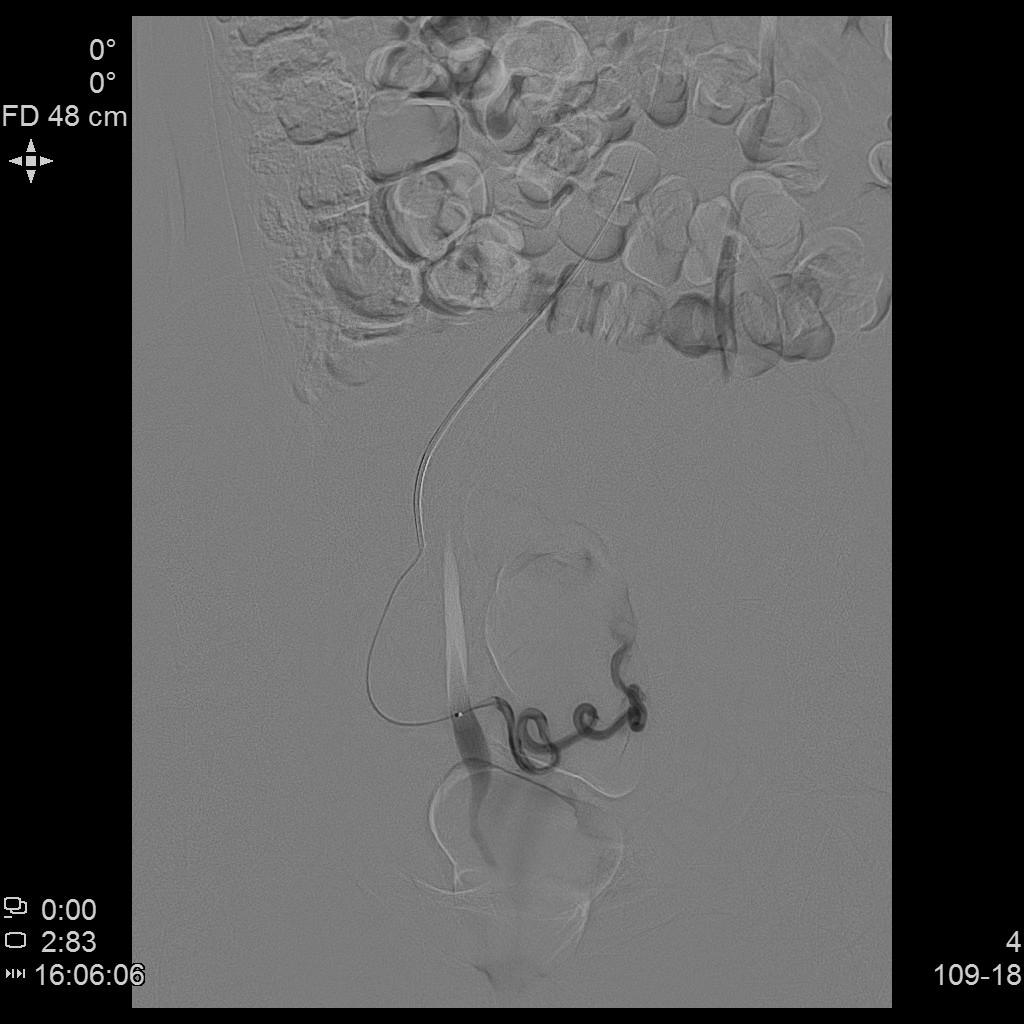

- DSA下行双侧子宫动脉栓塞治疗。

左侧子宫动脉造影

- 经桡动脉入路,分别超选择插管至双侧子宫动脉造影+子宫肌瘤栓塞治疗。

右侧子宫动脉造影